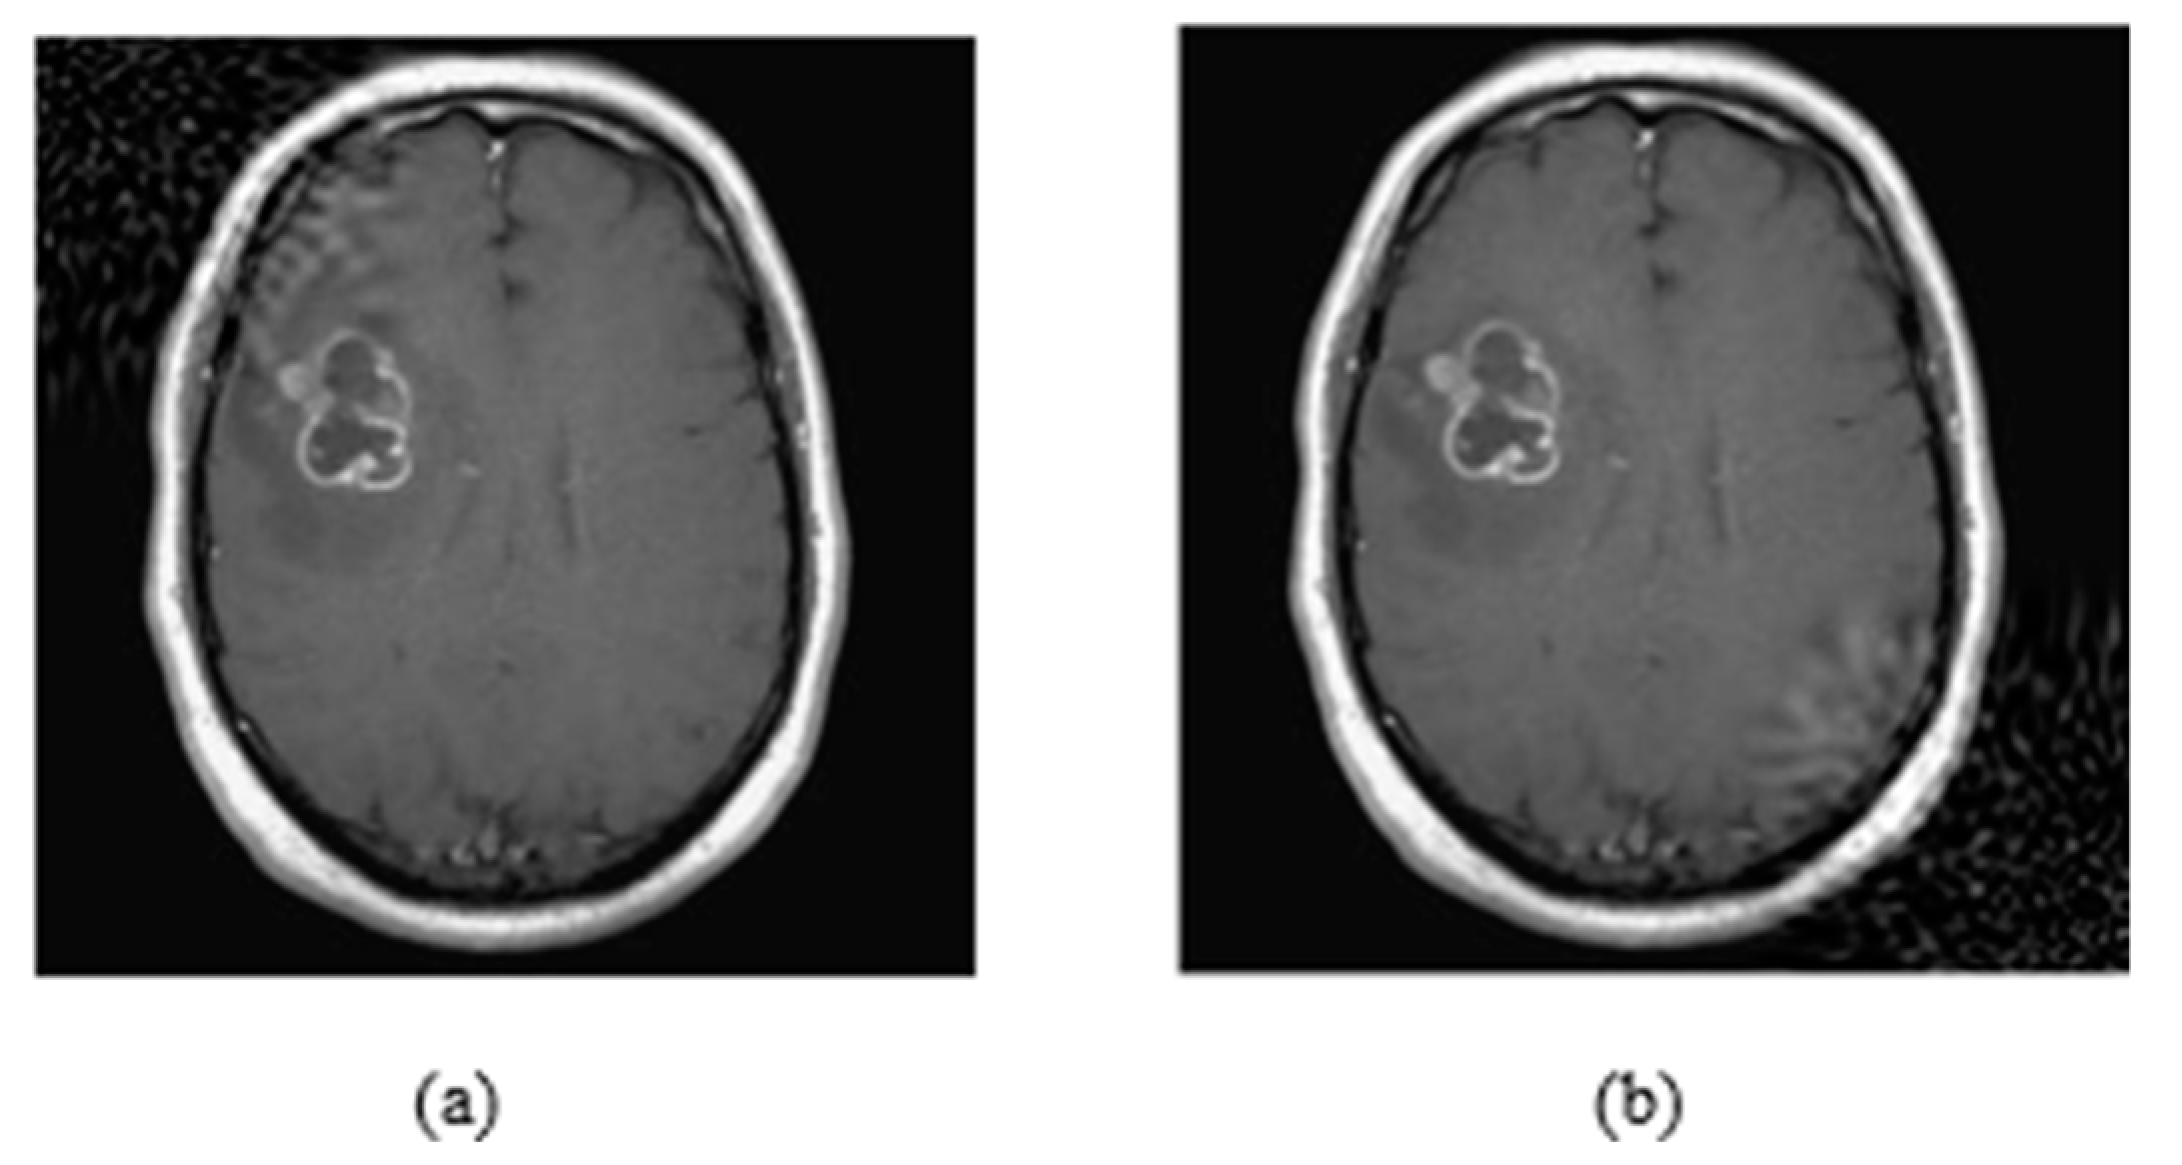

4.1. Datasets